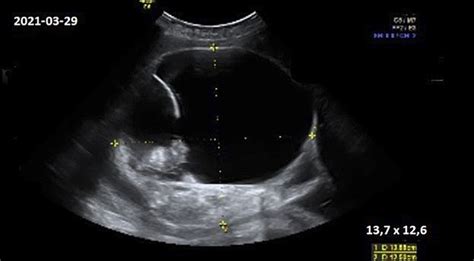

Dažniau stebimos su nėštumu susijusios komplikacijos, tokios kaip arterinė hipertenzija ir preeklampsija. Jei visą nėštumą stebima dažna hiperglikemija, kuri nėra tinkamai koreguota, žymiai didėja vaisiaus makrosomijos (didelio vaisiaus) rizika, daugėja vaisiaus vandenų, ir dažniau atliekama Cezario pjūvio operacija.

Vaisiaus makrosomiją sukelia motinos hiperglikemijos sąlygota vaisiaus hiperinsulinemija. Ji stimuliuoja augimo faktorių, skatinantį vaisiaus svorio priaugimą. Tai didina vaisiaus traumų ir Cezario pjūvio riziką. Kai aukšta nekoreguota glikemija, gali atsirasti ketonų.